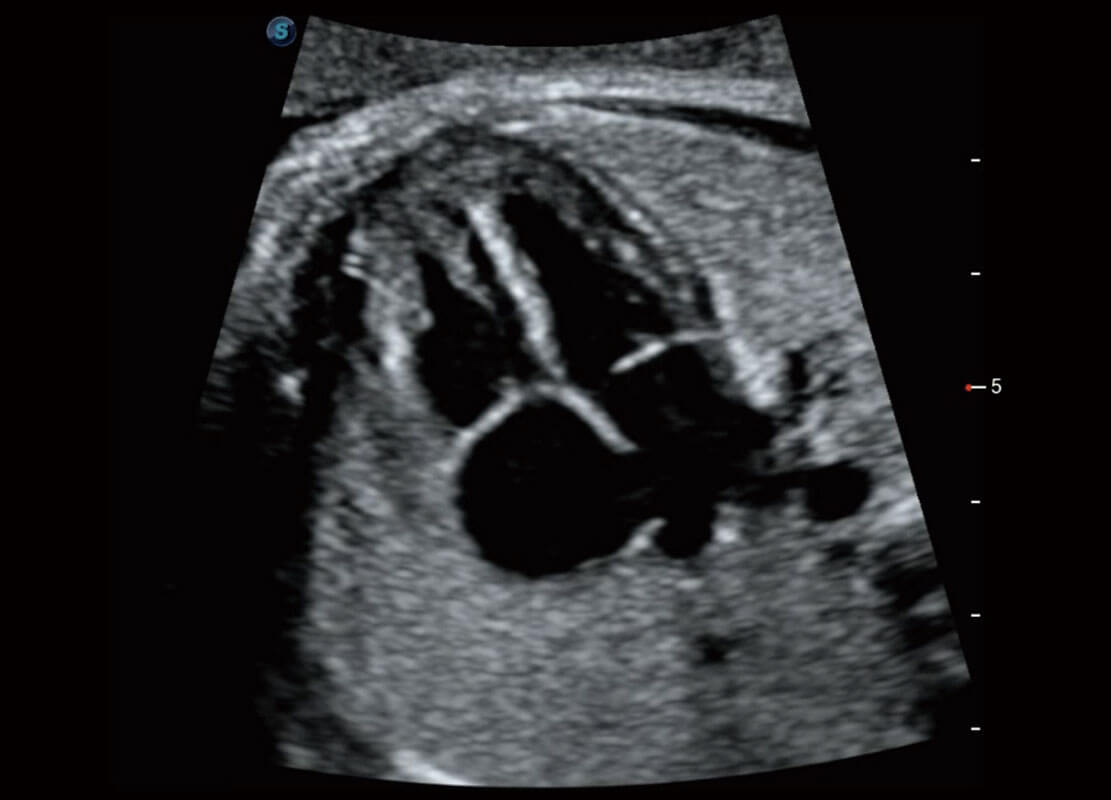

盆底超声

P60为盆底超声检查提供应用方案,多种腔内及腹部容积探头提供从二维、三维到四维的优异图像品质,实时快速三维容积数据获取,专业的测量工具包等人性化设计,为超声医生诊断提供有力保障。

S-Pelvic

能够简化盆底检查的操作流程,可在二维模式及三维成像模式下实现一键自动提取出标准切面、自动识别当前切面、自动测量,提升盆底检查的高效性,同时也能让青年医生快捷的获得准确的检查结果。